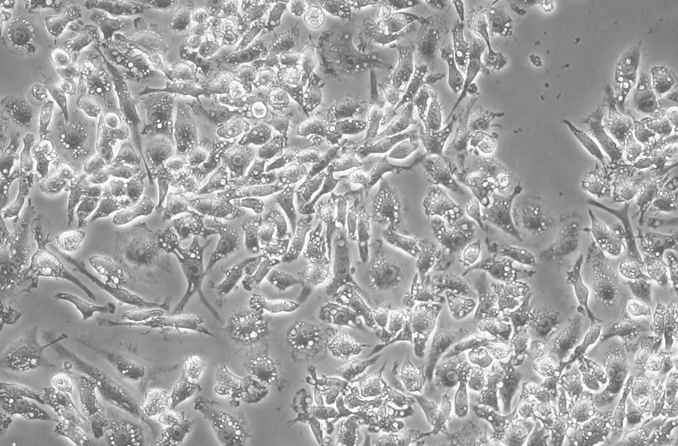

LPS诱导巨噬细胞

请问细胞周边的一个个连续白色圈大概是什么 发自小木虫Android客户端 |